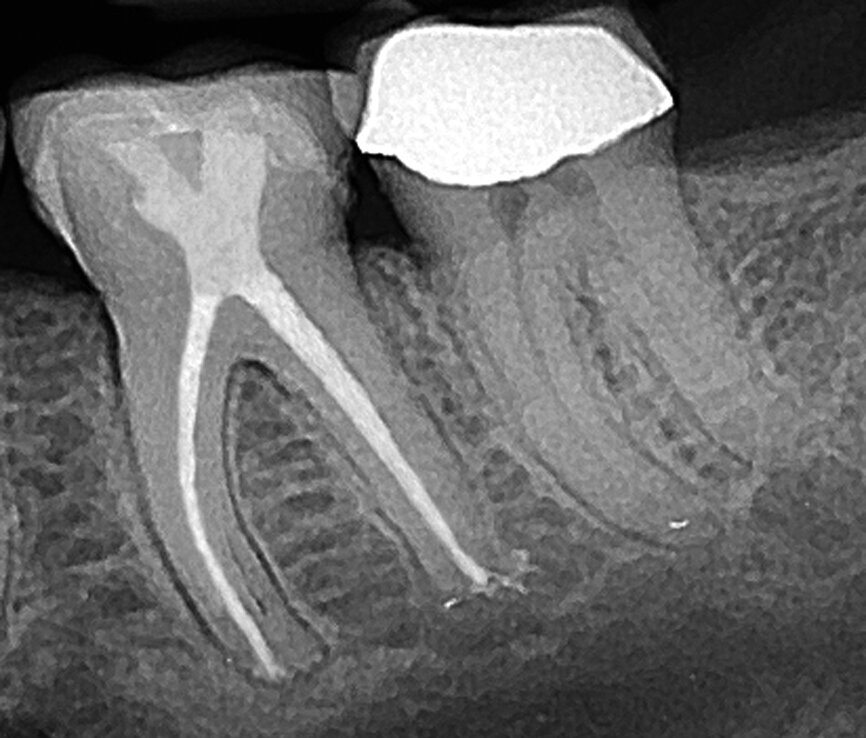

Fig. 5 : Radiographie postopératoire d’une molaire inférieure traitée au travers de la lésion carieuse mésiale et d’un autre petit accès au niveau de la fosse centrale. La préservation de la dentine entre les points d’accès est appelée configuration d’accès en « ferme ». (Photo : fournie par le Dr John Khademi)